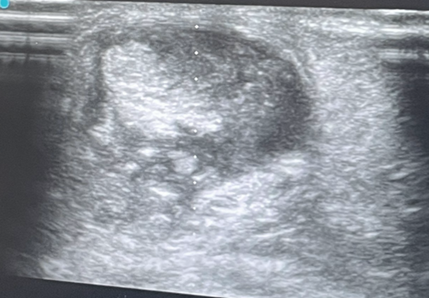

En corte longitudinal, se observa el tendón de Aquiles engrosado, hipoecogénico, con pérdida de la arquitectura fibrilar compatible con tendinosis, además de irregularidad focal compatible con secuela de rotura parcial. En corte transversal destaca calcificación intrasustancia y cambios degenerativos. Paratendón inferior y superior engrosados. Grasa de Hoffa con aumento de ecogenicidad sugerente de inflamación.